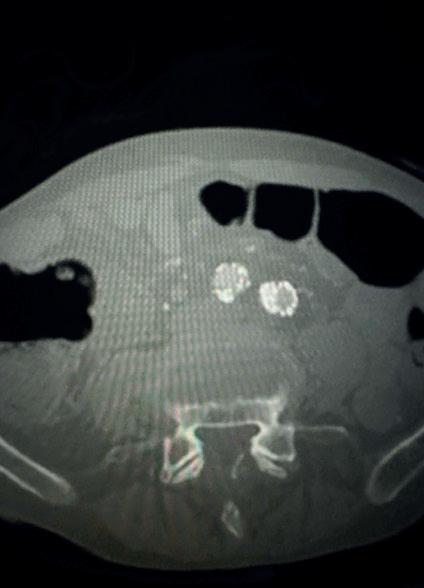

For those that qualify for intervention based on currently used criteria, vascular access is obtained in the standard fashion with ultrasound guidance. Caval venography is performed to ensure no anatomic abnormality, thrombosis or clot in transit. The right heart is then catheterised—I am a fan of the angled pigtail more so than a balloon-tipped catheter such as the Swan-Ganz as I feel its shape mirrors the anticipated trajectory. For each one of my PE interventions, a full right heart catheterisation is performed. A comfort with waveform analysis traversing right atrium, right ventricle and into the main pulmonary artery is paramount. These are standard displays in a cardiac catheterisation laboratory although not usual in the operating suite, so depending on your site of care, it is